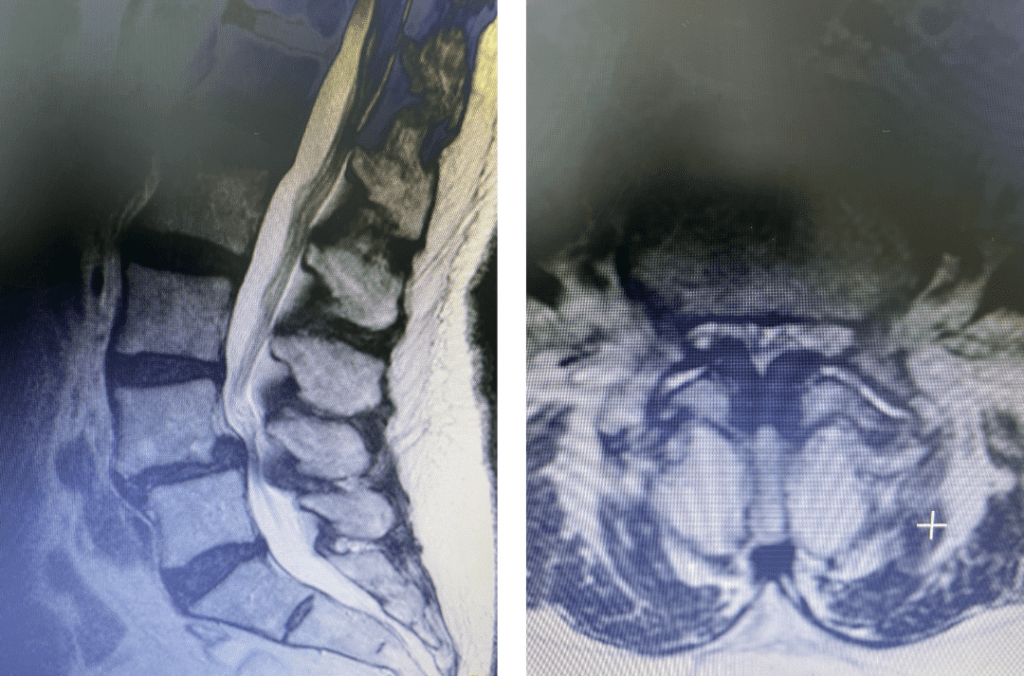

This 72 year old female had a long history of low back pain, leg pain, and scoliosis for which ten years ago she had a lumbar laminectomy followed by an instrumented L4-S1 fusion a year later. Since that time she had progressive low back pain and right lower extremity, weakness, and numbness. She presented with her leg symptoms being the biggest problem. MRI demonstrated a degenerative scoliosis with severe stenosis above the L4-S1 laminectomy and instrumented fusion. She had severe L2-3 and L3-4 stenosis. (Figs.3a,3b,3c 3d). After failing conservative management, she underwent an L2-L4 revision laminectomy and in situ fusion. She did well postoperatively. Considerations in performing a revision spine surgery is scar formation which initially makes it challenging to identify landmarks even in the region above that was not previously operated on. And of course during the dissection of compressive material on the dura, it is difficult to identify planes of separation and therefore an increased risk of a CSF leak. It was felt because of the severity of the scoliosis and her age we augmented the laminectomy with an in situ fusion, or a fusion with just bone graft without instrumentation. It is controversial whether a fusion is actually necessary in the case of a stable degenerative scoliosis with stenosis but the accepted approach is to perform a fusion If an instrumented fusion is considered it would require at least a T11-pelvis fusion. Since we performed only a 2 level laminectomy with a severely osteophytic spine, we compromised with an in situ fusion, reducing blood loss, operating time, and risk for infection. Because of the degree of spondylotic disease as a result of the stresses and strains on the spine given the scoliosis, the spine attempts to auto stabilize by forming these buttresses of arthritic material.

Fig 3a: Coronal T2-weighted MRI demonstrating significant detro lumbar degenerative scoliosis with a prior L4-S1 instrumented fusion. Note lateral listhesis of the L3-4; Figs 3b and 3c: Sagittal and axial T2- weighted MRIs showing severe lumbar stenosis above the prior L4-S1 fusion; Fig 3d showing an axial image T2-weighted MRI at the level of the prior L4-5 portion of the fusion showing no recurrent stenosis